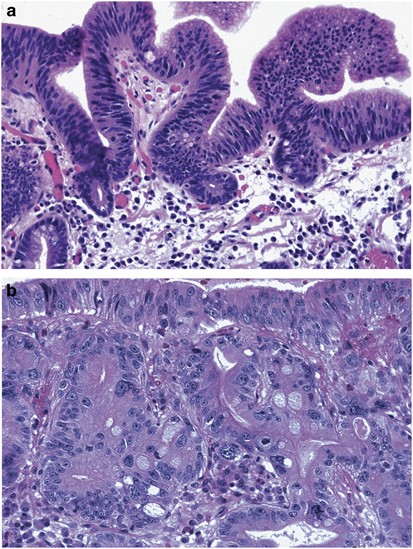

DİSPLAZİ

| Özellik | Detay |

|---|---|

| Tanım | Hücre olgunlaşma ve organizasyon bozukluğu |

| Bulgular | Nükleer pleomorfizm, mitoz ↑, polarite kaybı |

| Reversibilite | Erken evrede olabilir |

| Kanser riski | ✔ Prekanseröz |

| Örnek | CIN (serviks intraepitelyal neoplazi) |